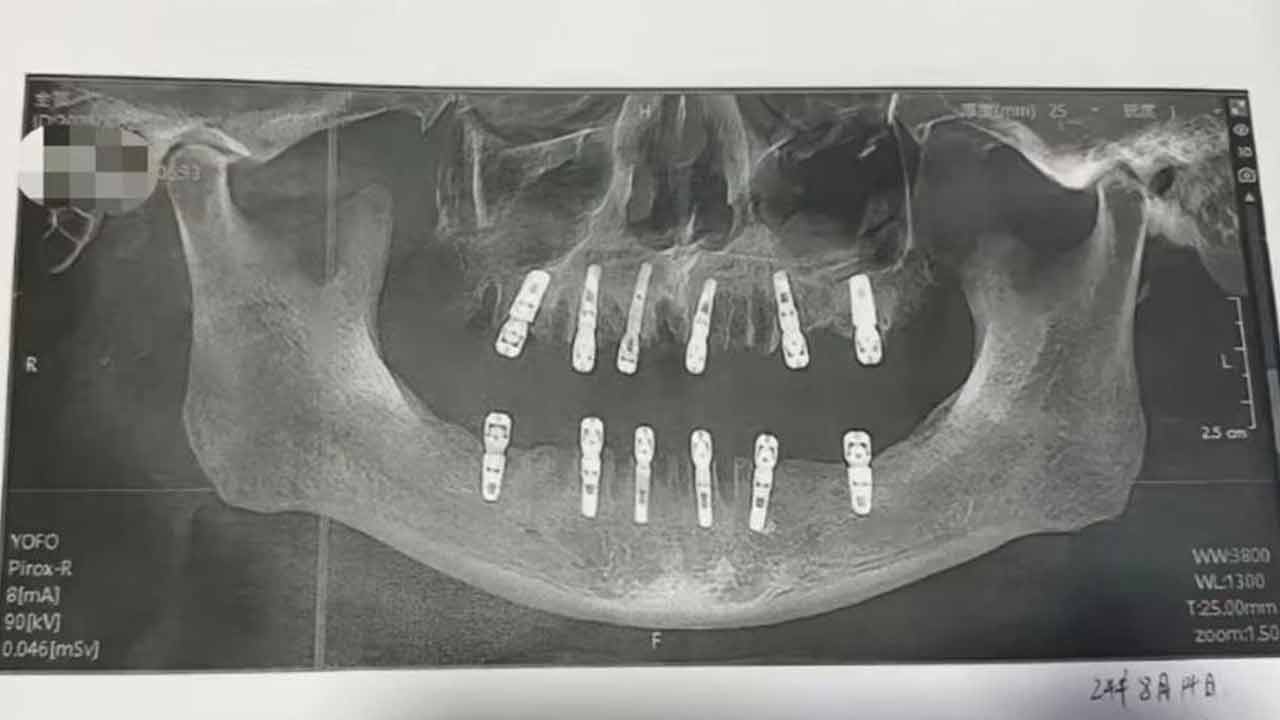

Heart Stroke | వ‌య‌సు పైబ‌డే కొద్ది చాలా మందిలో దంతాల స‌మ‌స్య( Teeth Pain ) ఏర్ప‌డుతుంది. ఈ స‌మ‌స్య తీవ్రంగా ఉంటే.. శ‌రీరంలోని ఇత‌ర భాగాల‌పై ప్ర‌భావం చూపుతుంది. అయితే ఓ వ్య‌క్తికి తీవ్ర‌మైన పంటి స‌మ‌స్య రావ‌డంతో డెంటిస్ట్( Dentist ) ద‌గ్గ‌ర‌కు వెళ్లాడు. ఒకే రోజు 23 దంతాలు( Teeth ) తొల‌గించి, కొత్త‌గా 12 దంతాల‌ను అమ‌ర్చాడు. ఈ శ‌స్త్ర చికిత్స జ‌రిగిన 13 రోజుల‌కు బాధిత రోగి ప్రాణాలు కోల్పోయాడు. ఈ ఘ‌ట‌న చైనా( China )లోని హిజియాంగ్ ప్రావిన్స్‌( Zhejiang Province )లో వెలుగు చూసింది.

చైనా( China )కు చెందిన హువాంగ్ అనే వ్య‌క్తికి తీవ్ర‌మైన దంతాల స‌మ‌స్య రావ‌డంతో.. స్థానికంగా ఎంతో ఫేమ‌స్ ఉన్న డీవే డెంట‌ల్ క్లినిక్‌( DeWay Dental Clinic )కు ఈ ఏడాది ఆగ‌స్టు 14ఇవ తేదీన వెళ్లాడు. రోగి అనుమ‌తితో డాక్ట‌ర్లు( Doctors ) ఒకేసారి 23 దంతాలు తొల‌గించారు. అదే రోజు.. కొత్త‌గా 12 దంతాల‌ను చేర్చారు. ఈ స‌ర్జ‌రీ విజ‌య‌వంతం కావడంతో.. హువాంగ్‌ను ఇంటికి పంపించేశారు డాక్ట‌ర్లు.